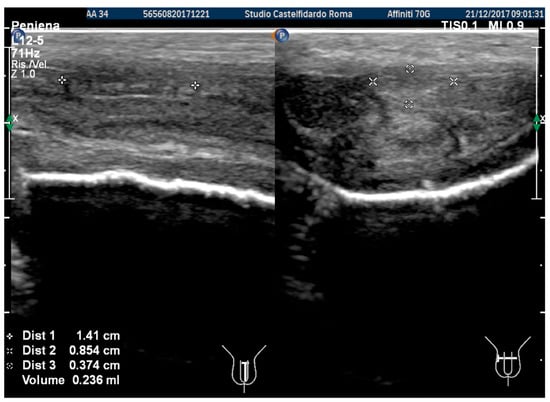

In the previous examination, we used the ultrasound machine Philips HD 15; subsequently, the ultrasound machine in our clinic was replaced by a new machine (Philips Affinity 70 G), which was used in the latter and subsequent follow-ups. The same doctor performed all the ultrasound examinations. The penile ultrasound showed the following dimensions: 14.1 × 8.54 × 3.74 mm (236 mm3 = volume) and the disappearance of the internal calcifications (Figure 10).

Compared to its initial measurement, the plaque had therefore undergone a 67.4% reduction in volume.

Figure 10. Ultrasonography of the penis after the 1st therapy cycle (longitudinal and axial views).